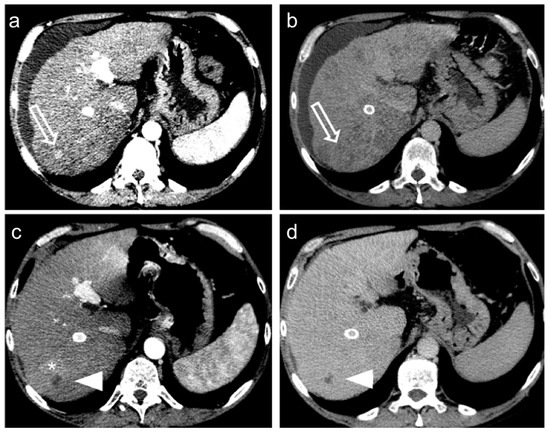

2. TACE Technique

3. Treatment Response Criteria